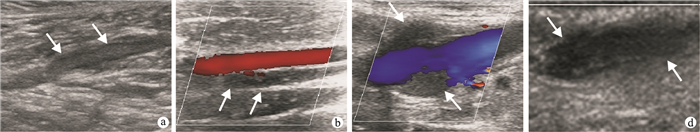

二維超聲:急性血栓處的靜脈管腔內有實質性低回聲充填,管徑均有不同程度的增粗,探頭加壓不能壓癟(圖 1a)。彩色多普勒超聲血栓處管腔完全阻塞時,無血流信號;管腔部分阻塞時,血流信號充盈缺損(圖 1b~1d)。

二維超聲與彩色多普勒超聲不同表現????a.?男,39歲,腰1椎體爆裂性骨折,二維超聲示肌間靜脈管腔內可見實質性弱回聲充填(白箭)????b.?男,43歲,腰椎骨折,彩色多普勒超聲顯示脛后靜脈管腔內未見血流信號(白箭)????c.?女,95歲,左側股骨頸骨折,彩色多普勒超聲顯示股總靜脈管腔內血流信號充盈缺損(白箭)????d.?女,83歲,右側股骨頸骨折,彩色多普勒超聲顯示頭靜脈管腔內管腔內未見血流信號(白箭)